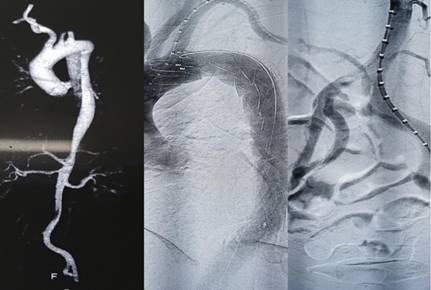

在急诊科与介入手术室等相关科室的共同努力和紧密配合下,顺利完成了主动脉腔内修复术,术后患者胸疼明显缓解,左下肢血运恢复良好,安返病房。

据田红燕教授介绍,急性主动脉夹层是一种具有致命危害的危重心血管疾病,非常凶险。所谓急性主动脉夹层,是指夹层发生时间在2周以内,这时候最大的风险是会造成血管破裂、大出血危机生命,另外夹层会堵塞远端部分重要分支血管引起重要脏器缺血坏死。目前治疗方式主要有:1.基本治疗:必须卧床,阵痛、降压、稳率等可以有效预防夹层的进一步发展。2.通过外科和介入治疗的方法,将夹层坡口进行封闭,达到治疗的目的。传统的方法是开刀将病变血管进行人工血管置换,随着医学的发展,大部分尤其是B型主动脉夹层通过介入微创治疗即刻解决,可以取得非常好的疗效。